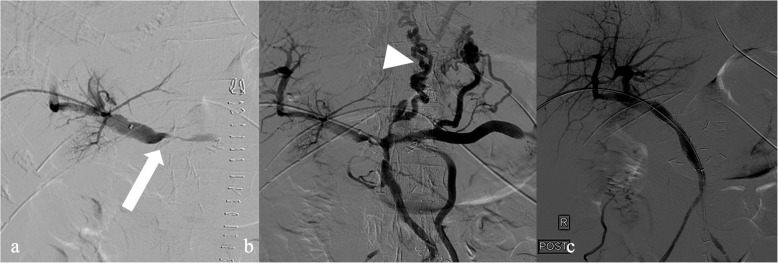

Case presentation: A 78-year-old female developed portal vein high grade stenosis after resection of an ampullary cholangiocarcinoma. The patient presented with acute liver failure and impaired coagulation function. Imaging confirmed transient ischemic changes of the hepatic parenchyma. Salvage attempt with a portal venous stent was decided to prevent irreversible liver damage. The procedure was successful with a satisfactory clinical outcome.